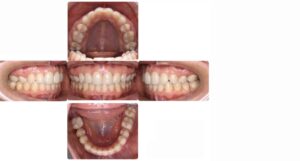

29歳の女性の患者さん。

「前歯が出ている、虫歯が原因で奥歯を2本失った」というお悩みで来院されました。

下顎左右の奥歯が失われた状態でしたが矯正治療でスペースを閉じて、上の歯は左右の小臼歯を抜歯して矯正用のアンカースクリューを併用して上の前歯を後ろに下げる治療を行いました。

結果、前歯の出っ張りが改善し自然に口を閉じられるようになり奥歯でしっかり噛める様になりました。(装置はハーフリンガル)

矯正治療後

※【診断】下顎左右第一大臼歯欠損を伴う上下顎前突【治療期間】約3年2ヶ月

【治療費用】検査料 ¥30,000(税別) / 基本料 ¥900,000(税別) / 調整料(毎月) ¥5,000(税別) / 保定装置 ¥30,000(税別)

【考えられるリスク】ブラッシング不良によるカリエス、歯肉退縮、歯根吸収、歯髄炎(歯の変色)